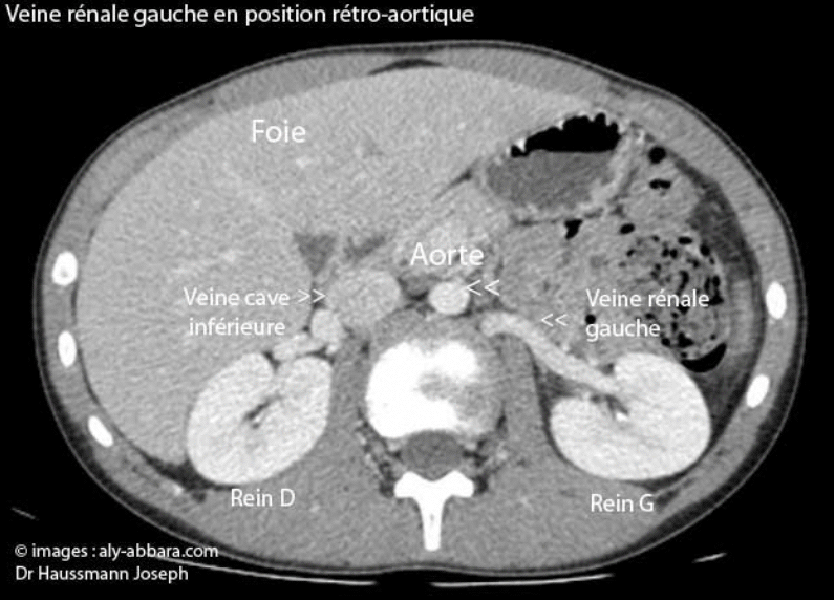

Veine rénale gauche en position rétro-aortique

(Scanner abdominal chez individu de 12 ans)

Il s'agit d'une position anatomique de la veine rénale gauche constatée chez 5 % de la population générale.

Cette veine et en position antéro-aortique chez 95 % de la population générale.

Imagerie et diagnostic réalisés par Dr Haussman Joseph. Extraction des images,

légendes, animation et publication par Dr Aly Abbara.